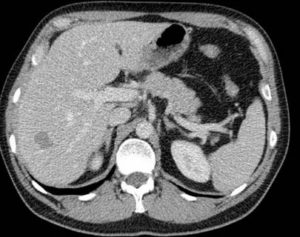

Все объемные новообразования, определяемые при проведении компьютерной томографии, разделяют в зависимости от ряда параметров: плотность, структура, форма, контуры, размер, локализация.

Плотность

Плотность – это основная характеристика любой ткани, измеряется на компьютерной томографии в единицах Хаунсфилда. По плотности бывают очаги гиподенсивные, гиперденсивные, изоденсные. По показателю плотности есть основания предполагать, что находится в структуре очага, присутствует ли жидкость, кровь, мягкотканные компоненты.

Особенности накопления контрастного вещества

Чем выше накопление контрастного вещества, тем лучше ткань снабжается кровью. И наоборот, чем медленнее паренхима накапливает контраст, тем хуже развита сосудистая сеть.

Чем активнее падает плотность тканей после завершения введения вещества, тем интенсивнее кровоток в пораженных местах печени.